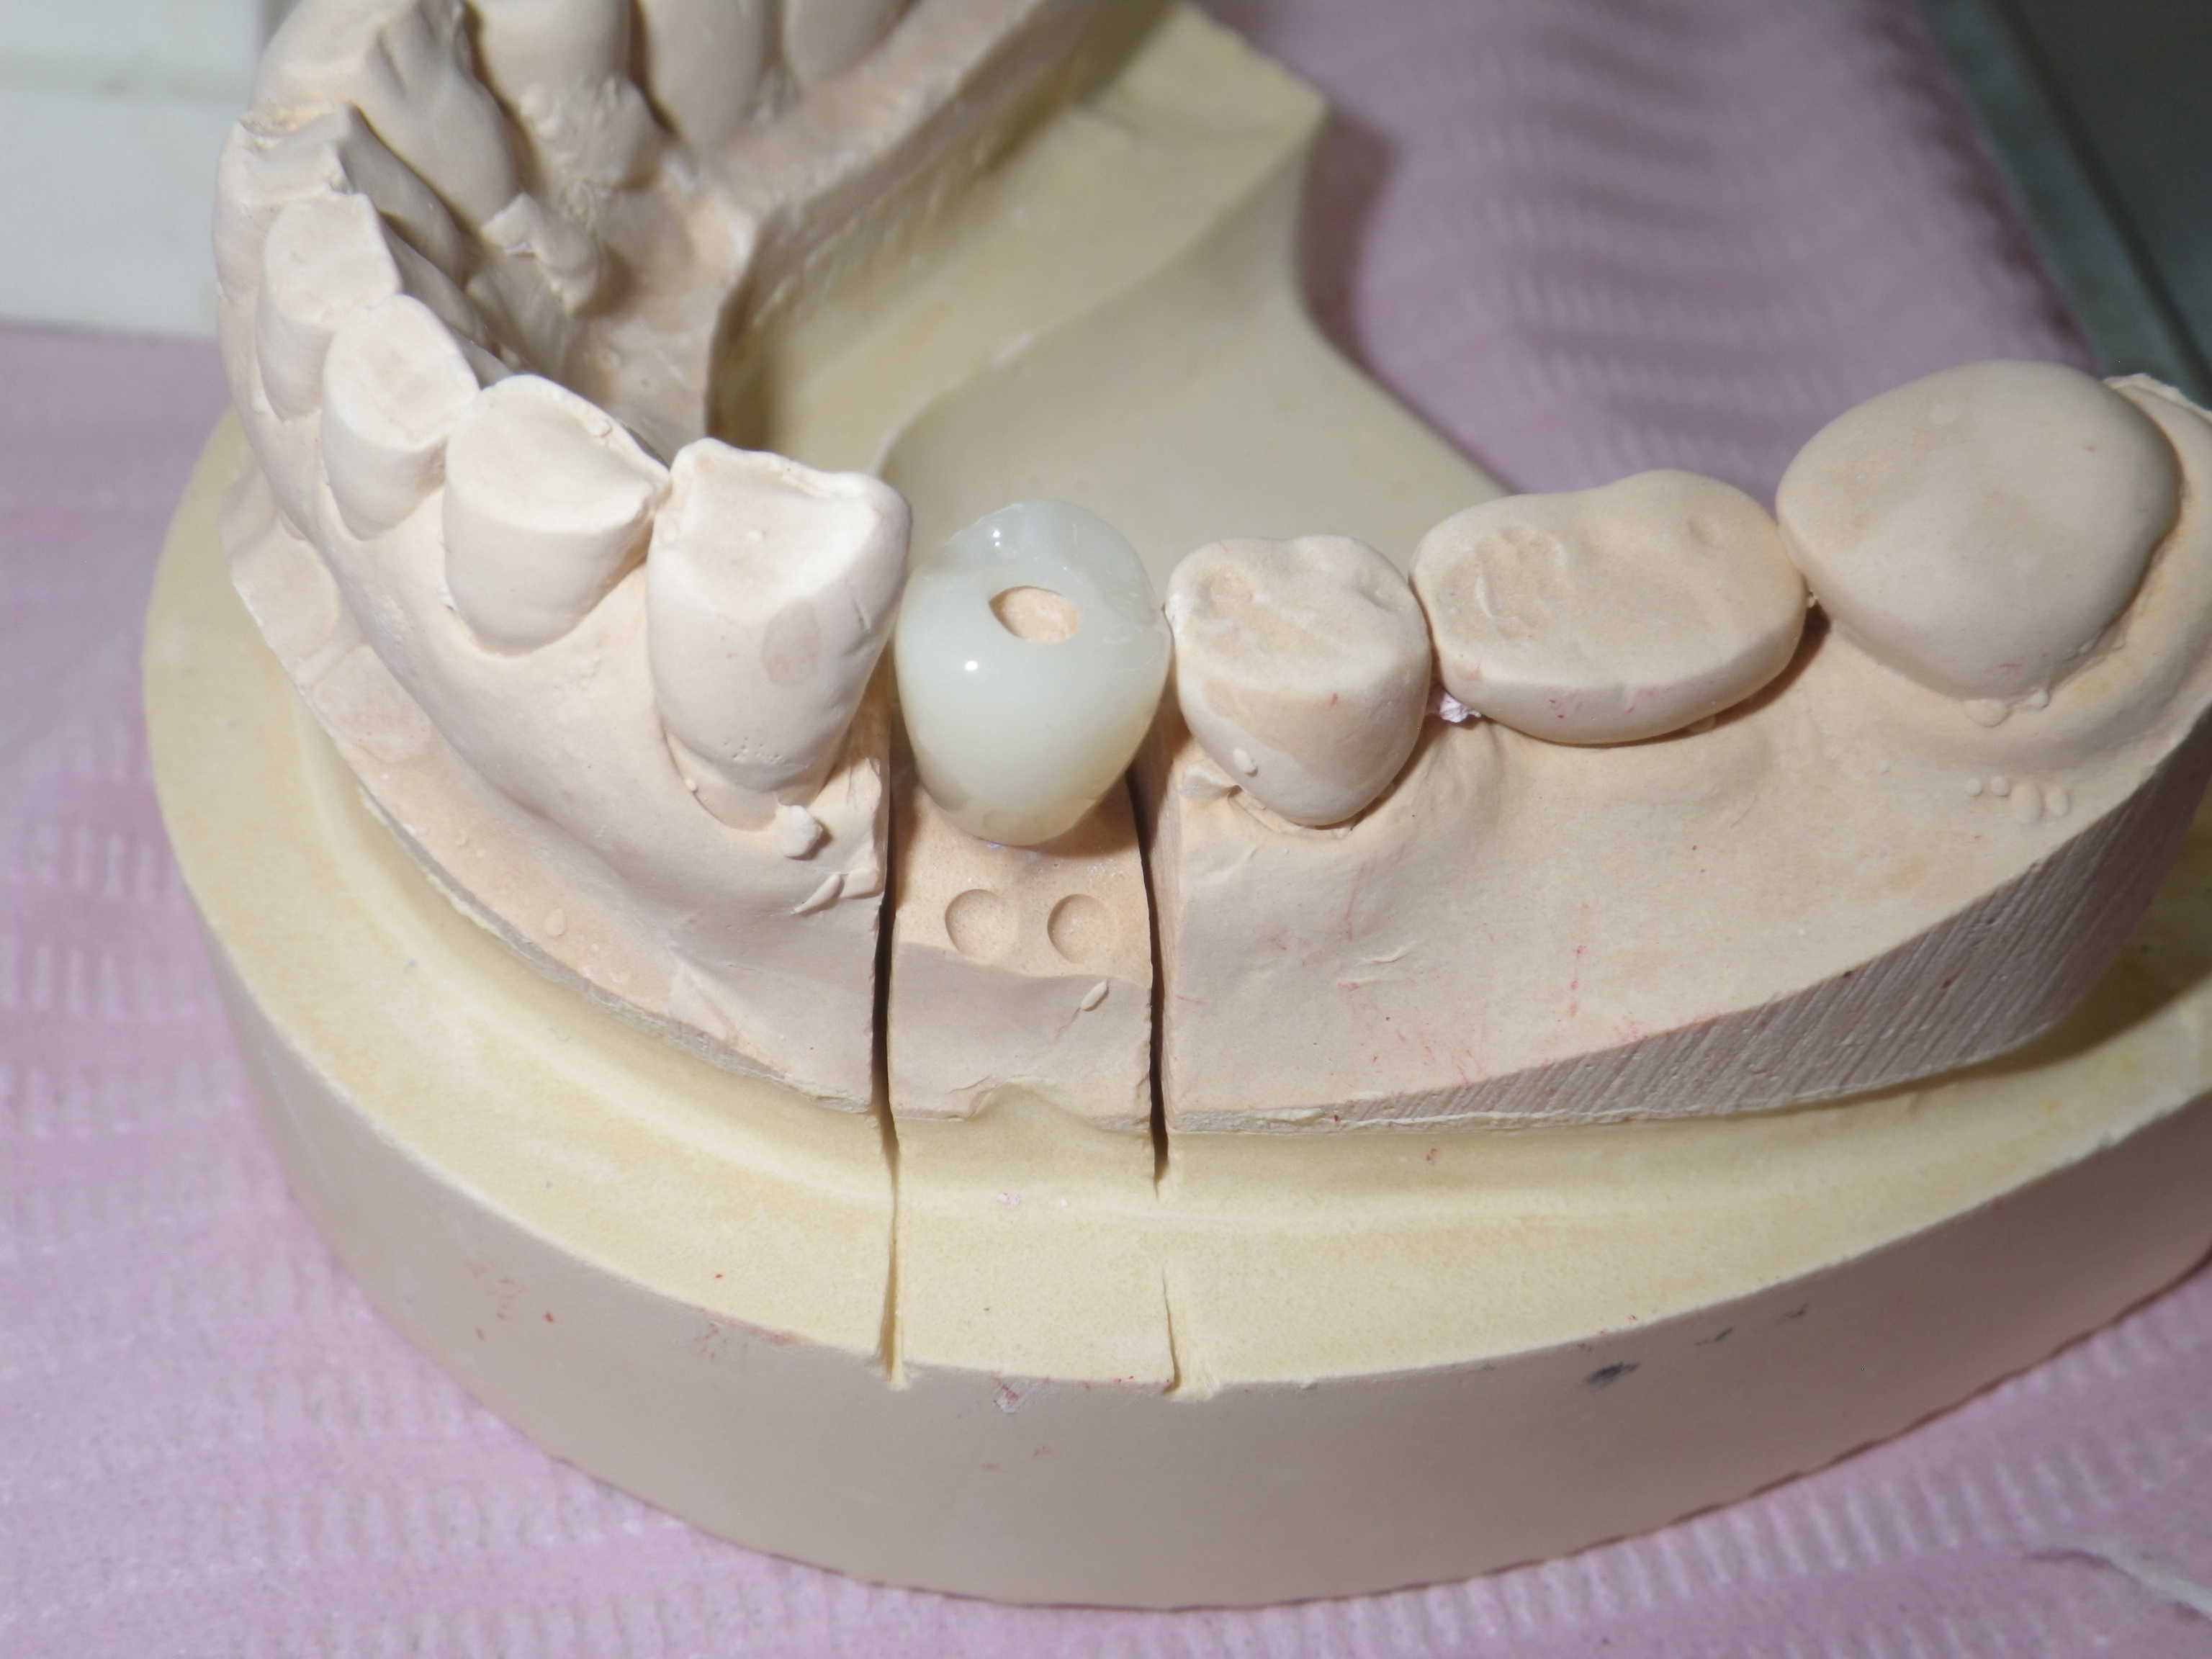

ねじを使わないインプラント

ネジを使わないインプラント

Biconインプラント

インプラント